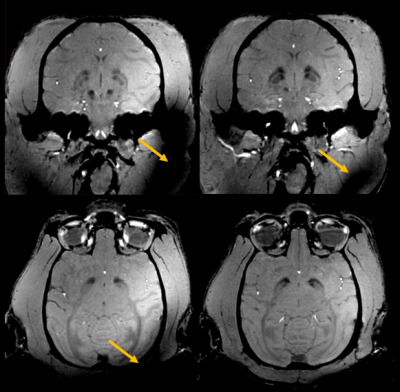

Figure 5 shows that, thanks to pTx kT-points [5], excitation homogeneity is reached in the entire brain, in particular in its lower part where the CP mode fails to bring up sufficient GRE signal. With 5 kT-points of 1.5-ms total duration, the NRMSE returned by our Bloch simulator was only 3% in the brain ROI for the 20°-target flip angle.

Pulse design with parallel transmission on NHP. Comparison of GRE MRI stemming from the default pCP mode (left) vs a dedicated kT-points pTx pulse design (right). Both acquisitions are registered and reconstructed in the coronal (top) and transversal planes (bottom) with 3D MPR out of 500µm isotropic acquisitions. Orange arrows points at strong signal losses. They are more prominent on the pCP acquisition than on the pTx acquisition. One can notice that even with the very same image windowing, the contrast is sharper for the pTx acquisition, especially in the deep gray nuclei.